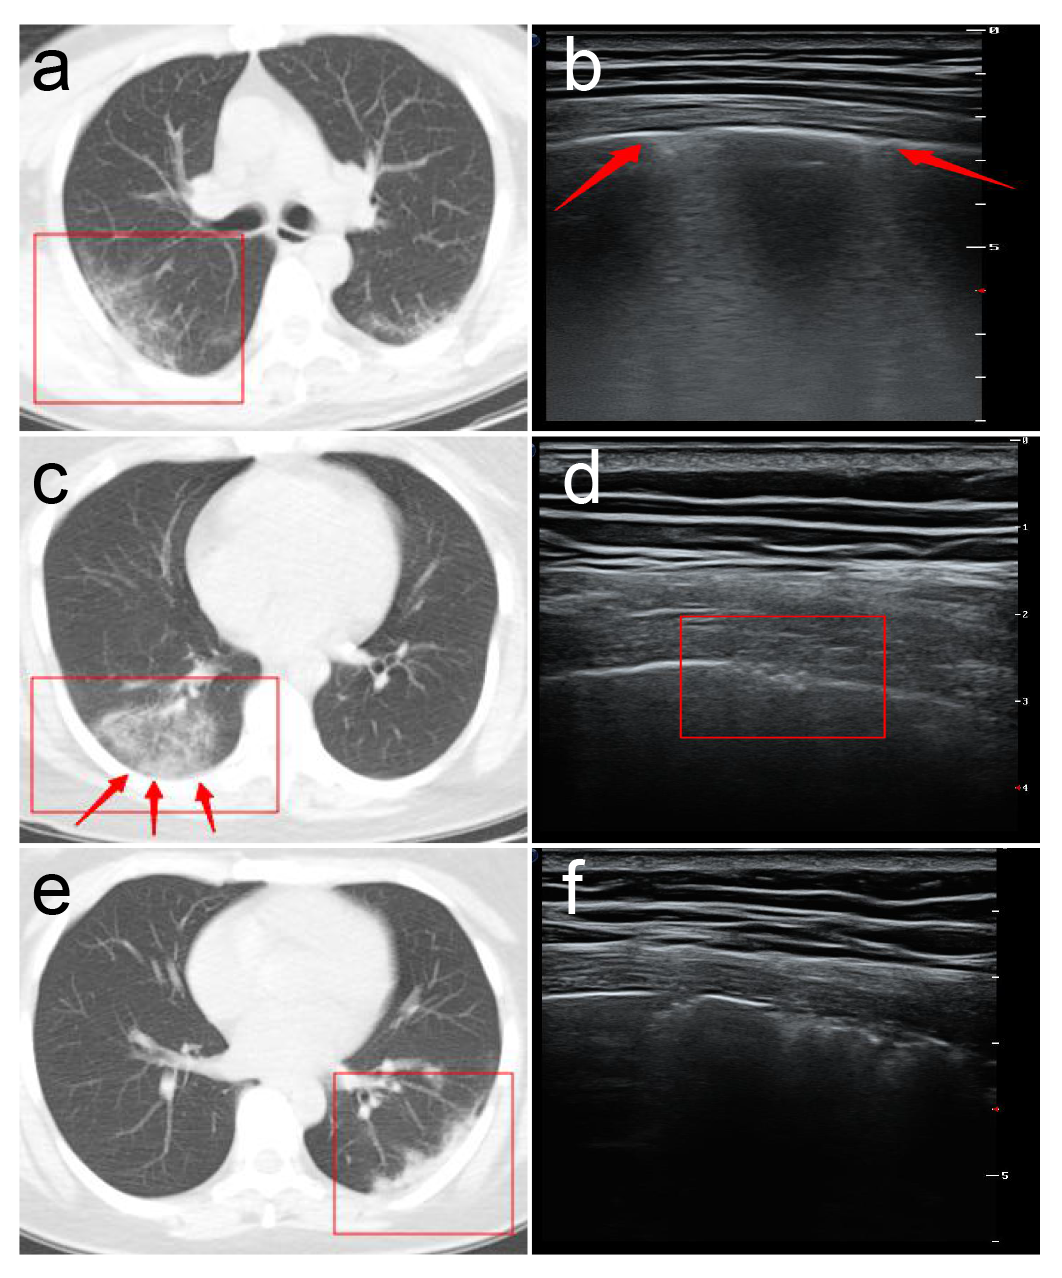

1.病灶部位多分布于双肺后野区。

2.超声探查可见胸膜线下多条不连续或连续融合B线(瀑布征),或弥漫性B线(白肺征),同时A线消失。与心源性肺水肿所致B线比较,冠肺B线融合现象更普遍,位置相对也比较固定,B线边缘模糊,无分叉征,起点位于胸膜下病灶较肺水肿B线起点圆钝(凸阵探头)。

3.高频超声显示胸膜线欠光滑、毛糙,连续性中断,主要是由于胸膜下肺泡及间质病变气体含量减少,声波反射减少所致。

4.胸膜下病灶可见多发小斑片样实变,长条样实变。

5.病灶内回声均匀或不均匀,多可见细小支气管肺泡充气征(早期、进展期多见。考虑次级肺小叶受间质炎性侵犯,间质水肿增厚,部分细小支气管及肺泡尚未受侵犯气体含量高所致)或支气管充气征(重症期或局部大片实变多见,考虑原因可能为局部炎症风暴所致大部细小支气管肺泡水肿实变仅留较大支气管或部分肺泡所致伴病灶后弥漫性B线,经观察部分发病时间较长病情趋于好转冠肺患者CT影像呈小结节样实变影,超声亦可见胸膜下结节样不规则回声影,后见融合B线,位置固定。

6.高频超声还可显示病变肺周的胸膜局限性增厚及胸膜下病变周围局限胸腔积液(线阵探头更清晰多数患者胸膜增厚约1-2mm,病灶周胸腔内局限性胸膜下积液约2-3mm)随病情进程有所变化。

7. CDFI超声显示非重症期新型冠状病毒肺炎(COVID-19)患者胸膜下实变病灶血流信号不敏感,随更换多台不同品牌新型超声仪器仍显示呈乏血流表现,具体原因可能与病变的病理性质有关,同时与病变进展时期有关,但应引起高度重视,因普通炎症所致肺实变彩色多普勒超声显示呈丰富血流信号,一般预后较好但新型冠状病毒肺炎(COVID-19)患者病变一般进展迅速,引起患者死亡,是否与肺组织未能迅速建立起丰富微小血管交换机制相关还有待于进一步研究,但值得肯定的是彩色多普勒超声相比其他医疗设备更能有效直观的了解实变肺组织血供信息,对临床医生预先判断患者预后及病情进程有重要的临床价值。